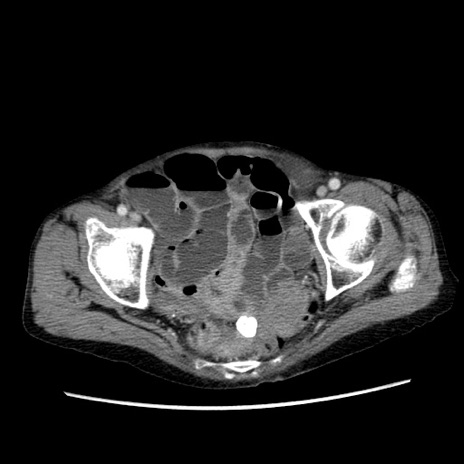

症例25(横断像)

【症例】80歳代女性

【主訴】胸のつかえ感

【現病歴】約9時間前に食後から胸のつかえた感じあり、嘔吐あり、来院。

【既往歴】胃癌(全摘)、胆摘、虫垂炎

【身体所見】心窩部に圧痛あり、反跳痛なし。

【データ】WBC 5700、CRP 0.05